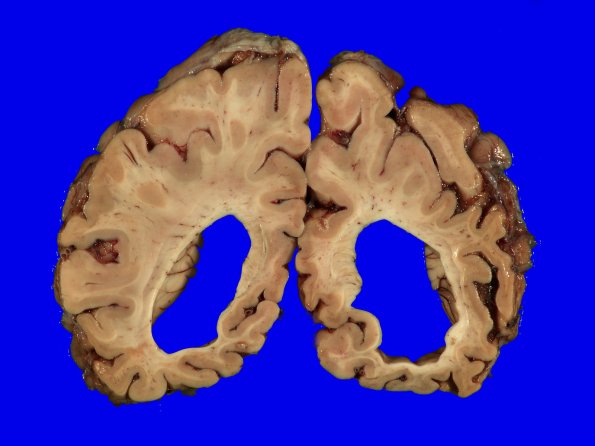

Washington University Experience | NEURODEGENERATION | Pick Disease | 1B10 Pick Disease (Case 1) 12

The parieto-occipital lobes are less involved, especially their superior portions.